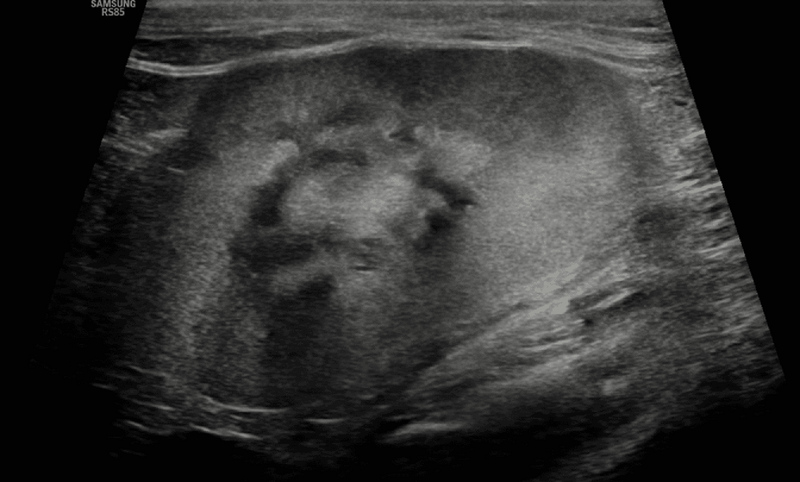

Zmniejszona wielkość nerek

Pomiary ultrasonograficzne wielkości nerek wykazują powiązanie z pomiarami makroskopowymi wykonywanymi podczas sekcji, choć należy spodziewać się pewnego niedoszacowania długości nerki.18 Zmniejszenia nerek (ryc. 10) oczekuje się w przypadku ich zwłóknienia, wielkość nerki może jednak nie korelować bezpośrednio ze stopniem zwłóknienia, jeśli jednocześnie występuje hiperplazja kompensacyjna, torbiele nerek lub pielektazja.8,17 Małe nerki mogą wskazywać na większy stopień zwłóknienia niż przerost kompensacyjny, co sugeruje bardziej zaawansowane stadium przewlekłej choroby nerek. Wielkość nerek wykazuje dużą zmienność u psów, a różnice między rasami ograniczają przydatność jej oceny.18 Dla psów zaproponowano wcześniej wskaźnik stosunku wielkości nerki do aorty, przy czym prawidłowy rozmiar nerki mieścił się w zakresie 5,5-9,5 cm,19 pomiar ten nie jest jednak powszechnie stosowany klinicznie. U kotów różnice między rasami są mniejsze, a prawidłowa długość nerki została określona jako 3-4,5 cm.8

Medium huguet ryc10 opt

Ryc. 10. Obraz w projekcji strzałkowej wyraźnie małej lewej nerki kota z towarzyszącą utratą prawidłowej morfologii nerki (na przykład ścieńczenie i hiperechogeniczność kory nerkowej, utrata zróżnicowania korowo-rdzeniowego, mineralizacja, nieregularne brzegi).